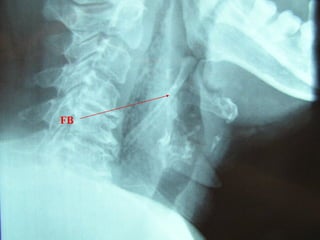

Lateral neck XR

Deep Neck

Infection

•Normal retropharyngeal

space on lateral neck XR is

up to 1 vertebral body

width from C5 and below.

Widened

retropharyngeal space

on lateral neck XR

•Up to half a vertebral

body width from C1 to C4

is normal